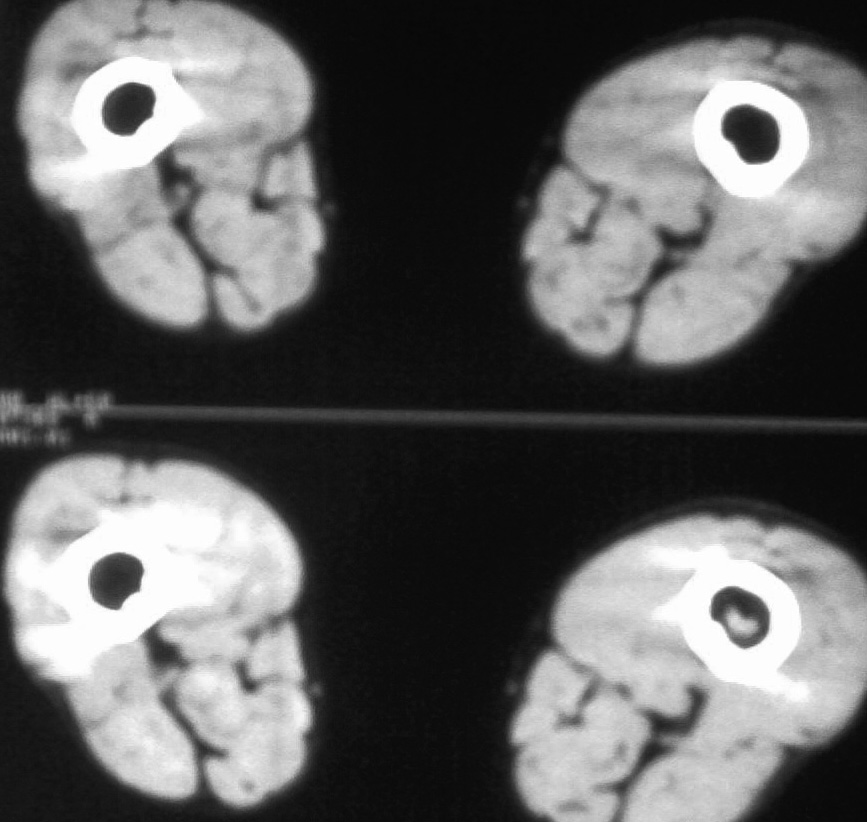

中央型纤维肉瘤主要破坏松质骨,x线表现以局灶性透亮区为主,其中无成骨现象。边缘参差不齐。中间偶可有散在小钙化点,邻近骨皮质局限变薄,轻度膨胀,虽常被穿破,然多无骨膜反应,有些病例,病变范围较广,骨小梁排列紊乱夹杂有骨质破坏的小斑点状透光区,分布弥散,偶有少量骨膜新骨形成。周围型肿瘤常位于软组织中,呈圆形或卵圆形阴影,密度较肌肉影略离,肿块中可出现少量均匀钙化点。

发病率低,至少比骨肉瘤的发病率低10倍。无明显性别差异,或仅轻微偏重于男性。可发生在任何年龄段,在15~60岁之间的分布没有什么差别,发生在青春期前为个别病例。

好发于以下部位,按顺序排列为股骨远端、胫骨近端、股骨近端、肱骨近端及骨盆,约50%的病例发生在膝关节周围,20%在四肢骨近端,20%在躯干骨,很少在手足骨。

在长骨,一般位于到骨干的一端或干骺端;在成人常侵及骨骺,纯粹定位于骨干者少见。

疼痛是主要症状。在低度恶性的纤维肉瘤中,肿胀轻且晚,有时无肿胀,但当纤维肉瘤侵袭性较强时,肿胀则较早出现。纤维肉瘤的病理性骨折多见。